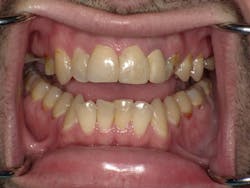

Direct view one month after hygiene treatment and restorations placed teeth Nos. 7, 8, 9.

David paid cash and was on a limited income, so he chose to deal with the biggest problems first. We completed a comprehensive exam with x-rays and full probing. Rampant decay was noted as a result of drug use. Maxillary teeth Nos. 3, 13, and 14 all had had previous root canal therapies, but were decayed to the bone levels with only retained root tips present; no abscesses were present. Teeth Nos. 3, 13, and 14 all have hopeless prognoses and are planned for extraction, and implants will be done when the patient is ready. Nos. 8, 9, and10 were repaired at the initial visit as decay was close to the nerve space and causing pain. The images in this article were taken after anterior fillings were completed.